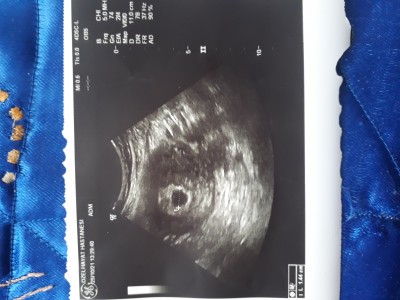

Kızlar dün gece kahverengi alıntım oldu doktora gittim sorun yok dedi ilaç verdi geçen perşembe kesem 6mm bunu bunu yenı çekti doktorum ama kaç mm olduğunu söylemedi anlayan varsa yardımcı olursa sevınırım

Fotoğraf pek net değil ama sanırım sol alt köşede yazıyor. Keseyi olctugu nokta nokta yere bak L1 yazıyor galiba birde sol altta onun ölçüsü yazıyor sanırım fotoğraf net değil

1.44 sm yazıyor galiba

Yanı kaç mm olmuş eşim hesapladı matematiği iyidir 10mm dedı